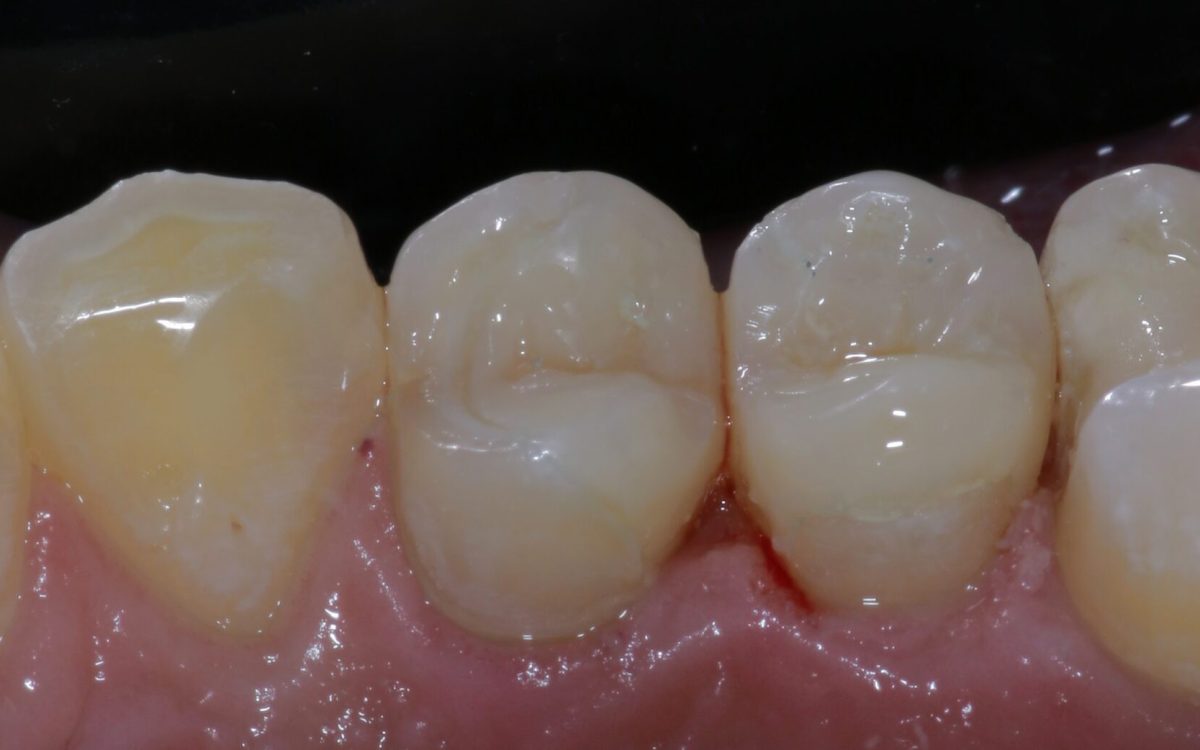

Fog betét (inlay, onlay)

A betét olyan, fogtechnikus által készített esztétikus fogpótlás, mely a fog koronai részén helyezkedik el mint egy nagyobb tömés és bizonyos esetekben nagyobb védelmet képes nyújtani, mint a fogtömés. Betéteket a kis-és nagyőrlő fogakra helyezhetünk! Élethű, strapabíró és megfelelő szájhigiénia mellett sokáig képes védeni a fogat.

Abban az esetben készítjük, amikor a tömés már nem tudná ellátni a fog védelmét.

Hogyan készül a fogászati betét?

Miután megállapítottuk, hogy tömés helyett betétre lesz szükség, lenyomatot veszünk. Ez alapján a fogtechnikus elkészíti a betétet, amit kb. egy hét múlva rögzíthetünk a fogra. Ezt a fogra próbálva még igazíthatjuk – pl. elvehetünk a magasságából, ha páciensünk így érzi kényelmesnek. A lenyomat és a kész betét közötti időre ideiglenes betétet helyezünk a fogba, hogy érzékenyésgét csökkentsük és stabilitását megpróbáljuk a végleges pótlás érkezéséig megóvni.